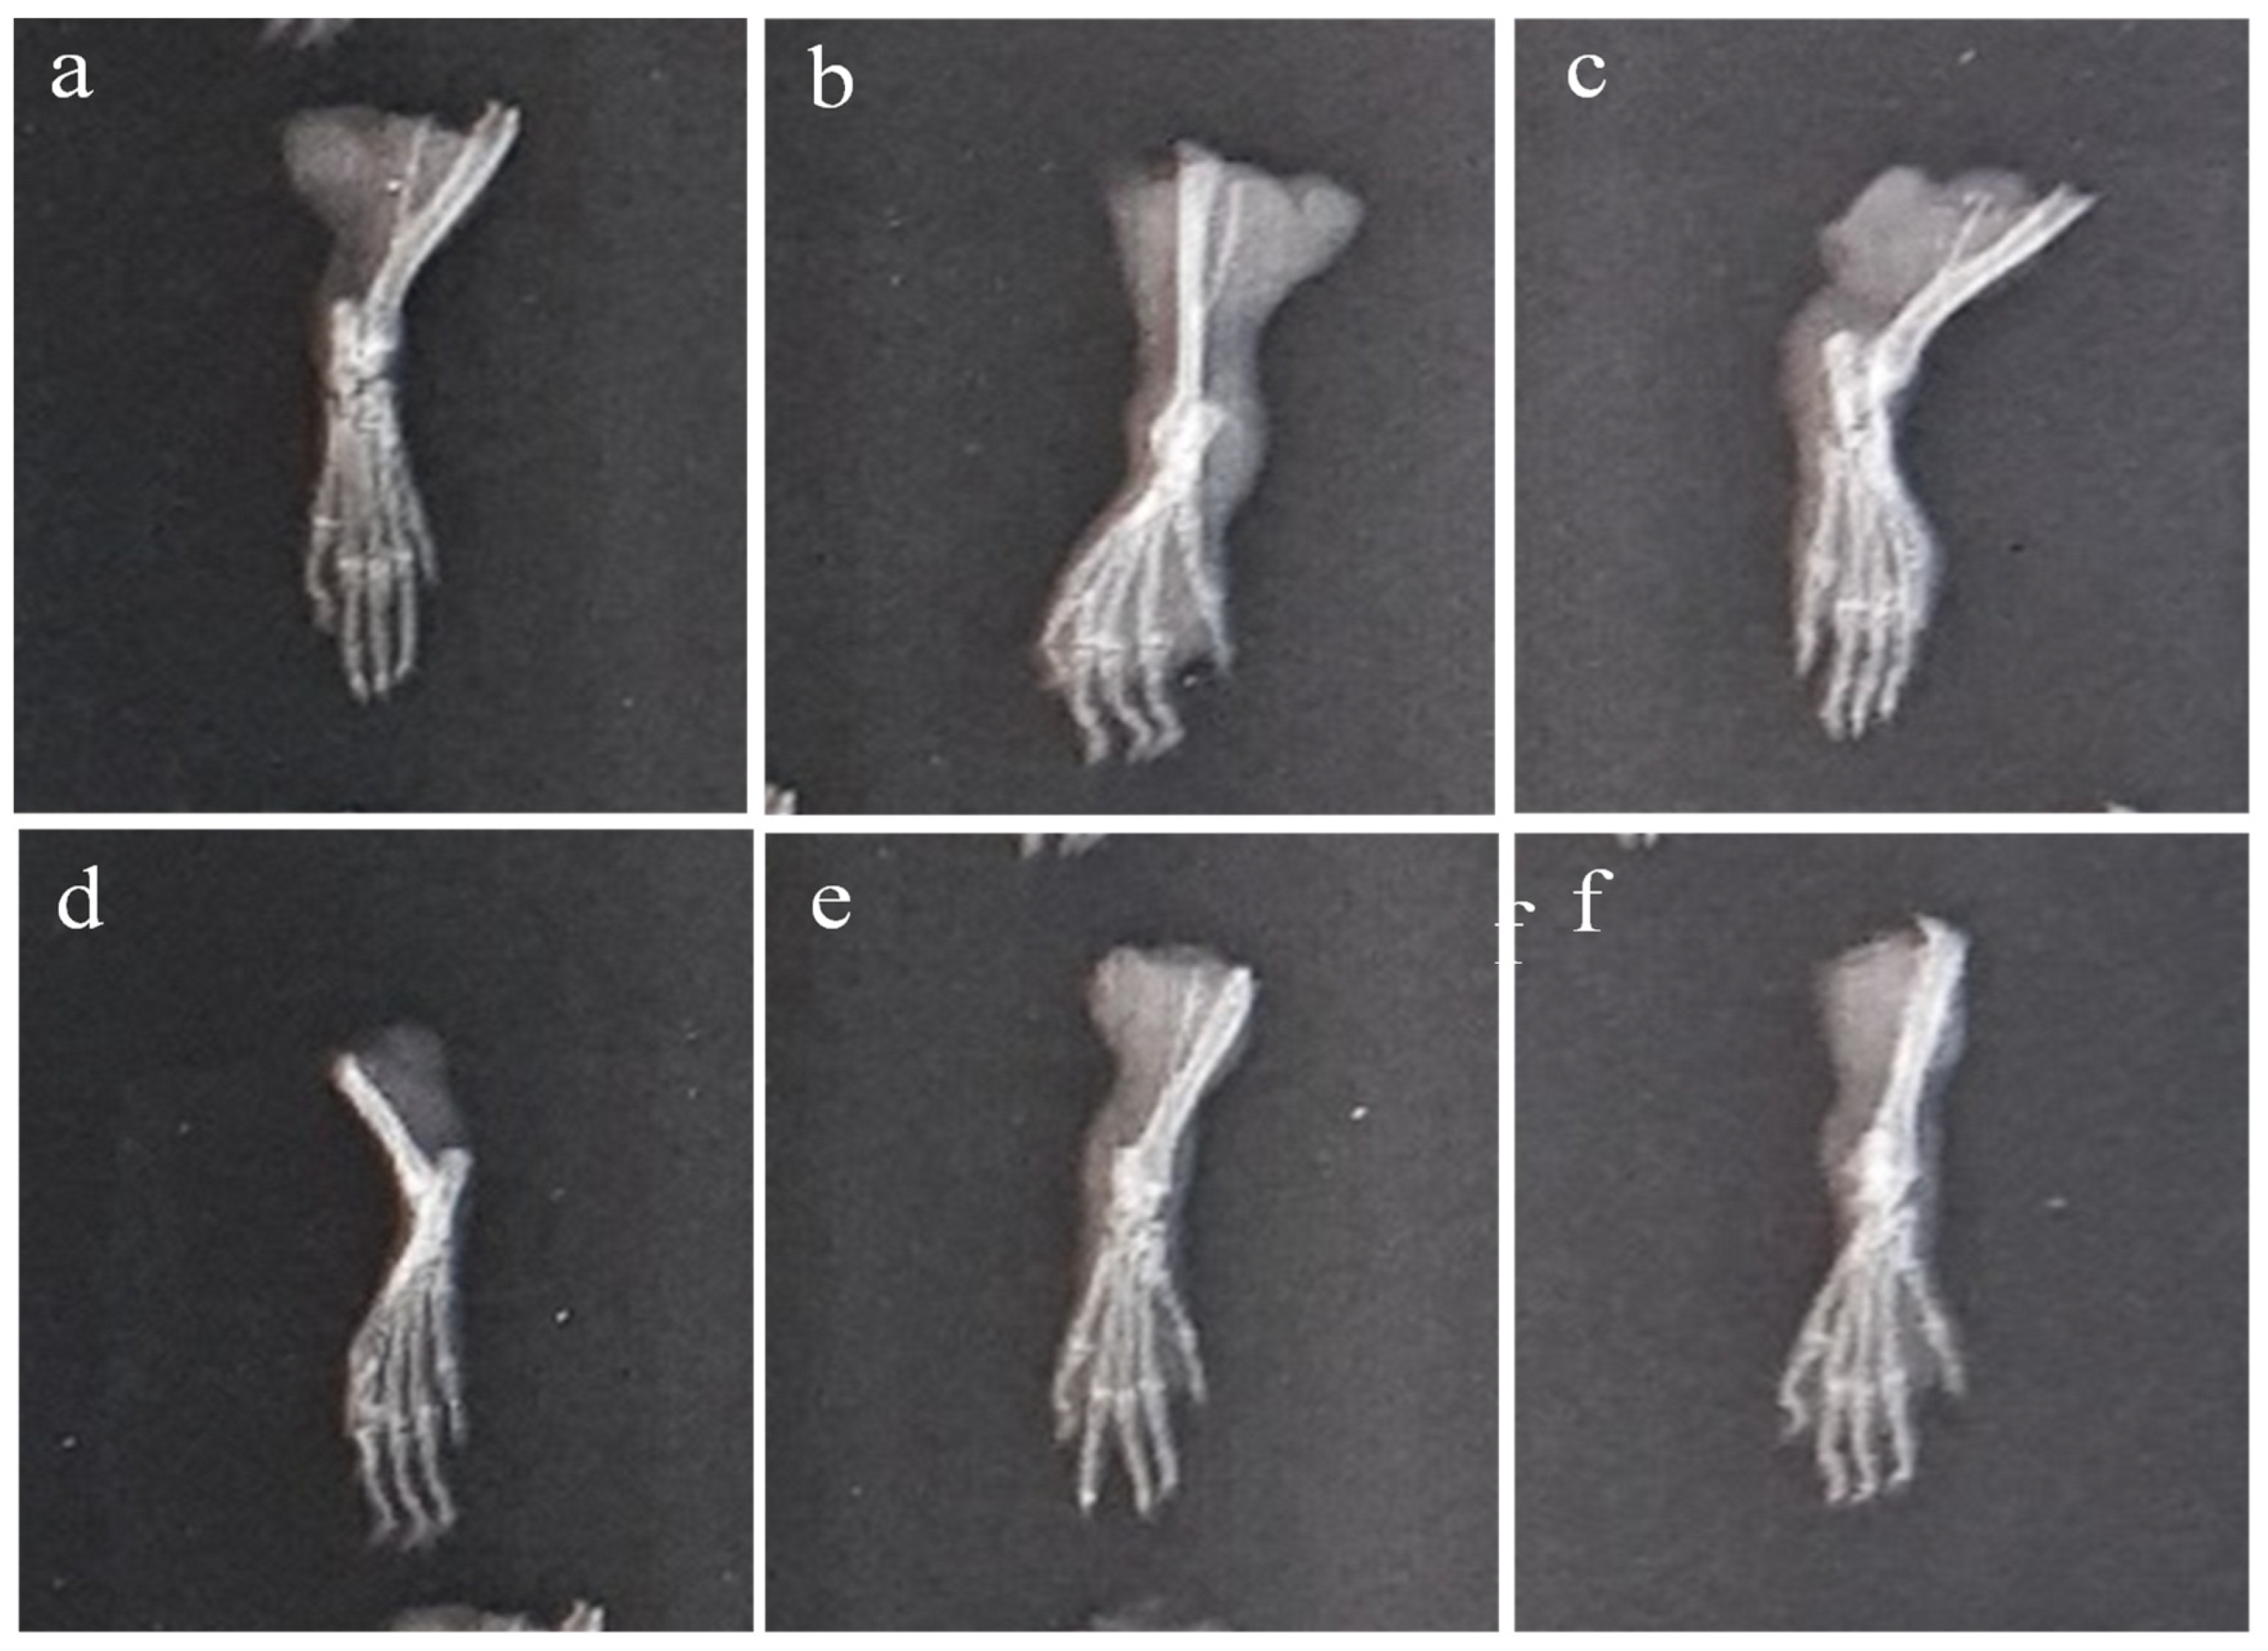

2.6.3. X-ray of Left Hind Paw

4.7.9. Body Weight Measurements